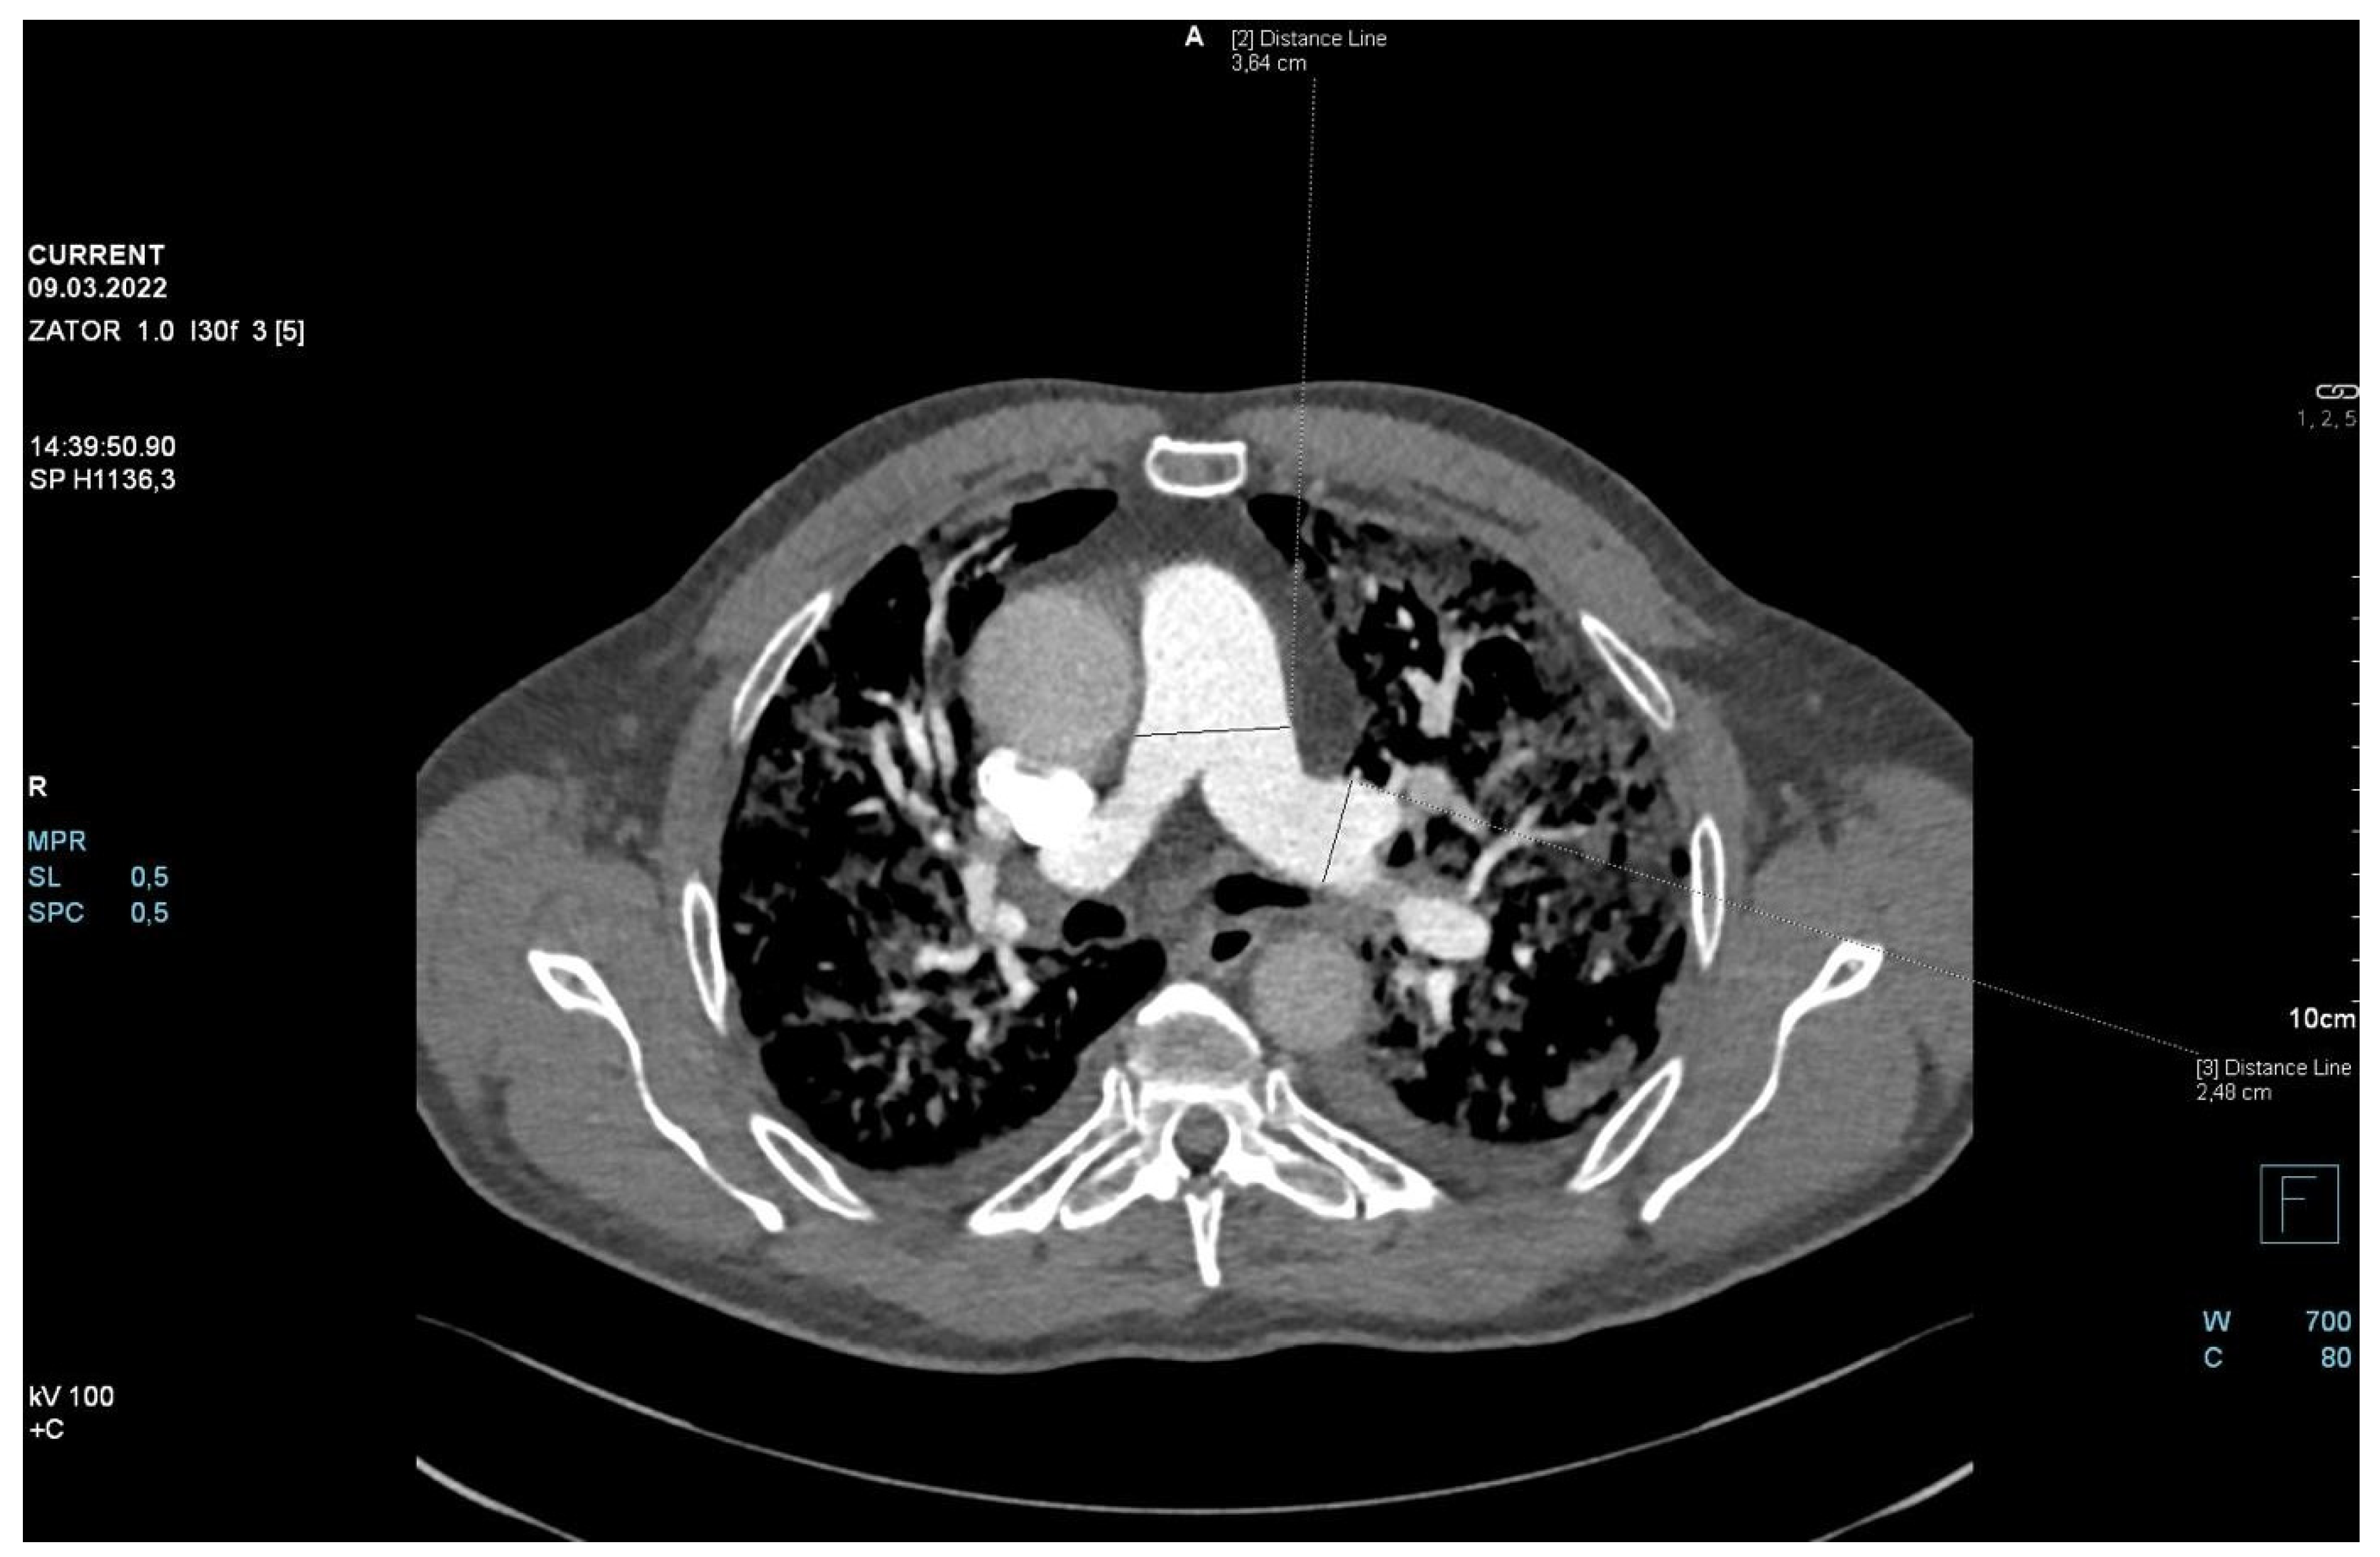

The patient required oxygen therapy, and initially, due to a lack of diagnosis, he received empirically broad-spectrum antibiotics (meropenem, linezolide). On laboratory testing, a further increase in inflammatory and coagulation biomarkers (CRP, ferritin, interleukin-6, D-Dimer, fibrinogen) was observed. Blood cultures as well as a respiratory PCR multitest were negative. Due to the dynamic increase in D-dimers and the elevation of cardiac biomarkers (BNP, NT-proBNP) along with dyspnea, an angio-CT was performed. It excluded pulmonary embolism, but it revealed widening of the pulmonary trunk and pulmonary arteries, as well as alveolar compaction in both lungs and bilateral pleural effusion. Pulmonary edema was diagnosed (Figure 2, Figure 3 and Figure 4).

Figure 3.

Angio-CT scan.